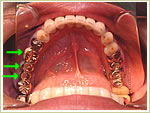

●骨作りを行った症例

38歳 女性 インプラント埋入数:6本 画像拡大

治療後

治療後 治療後 治療後